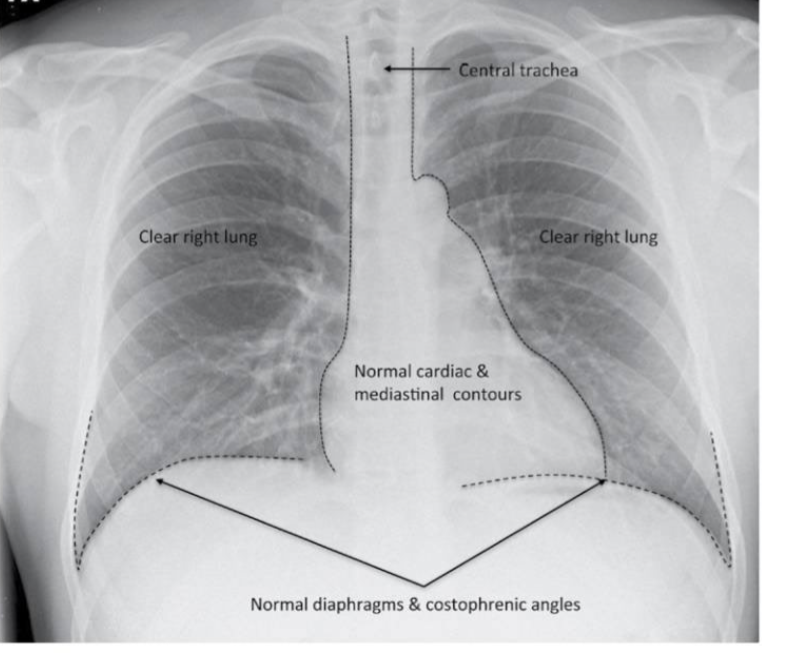

what type of view is shown?

PA view

The ABCDEs of CXRs are Airway, Breathing, Circulation, Disability, and Everything else. This mnemonic helps to systematically evaluate chest X-rays for pathologies.

trachea to the carina, and the main bronchi (see if the carina too wide- greater than 100 degrees, or if the bronchial narrowing or dilation)

what can be look at to assess breathing in CXRs?

lung expansion/volume (should count 10 rubs posterior rib bilaterally), if one lung is larger than the other and are there areas of density, look at the crisp costophrenic angles - trace the lateral margins of lung to costophrenic angle. should look at the hemidiaphragms, and the cardiac borders (should be able to clearly see the L and R heart borders)

what can be seen in relation to circulation on the CXRs?

can check cardiac position, assess cardiac size (cardio width should be less than 50% of the thoracic width) check the position and size of the aortic arch, check the width of the upper mediastinum, and look at the hilar vessels